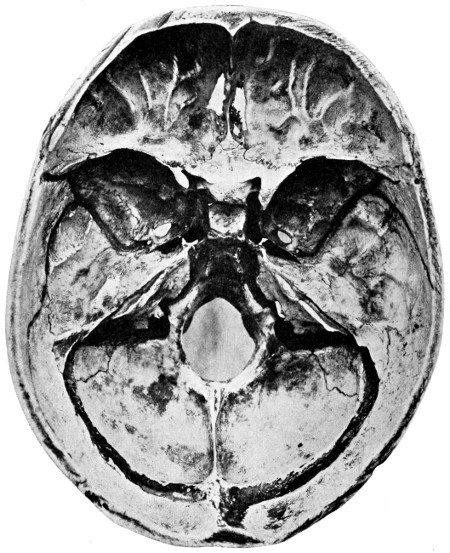

29 A and B. The base of the skull and the base as seen on transillumination 70, 71

30. Plan of the base of the skull 77

50 A and B. The inner aspect of the skull and the same seen on transillumination 137

51. To illustrate compression of the brain as produced by an extra-dural hæmorrhage from the middle meningeal artery[x] 141